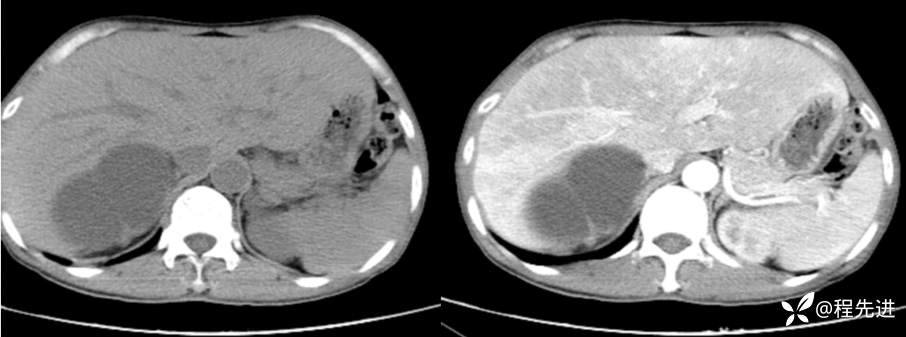

CT平扫+增强

左平扫,右增强